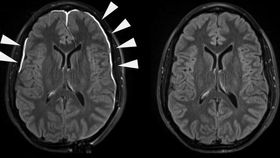

The team of researchers from the National Institute of Health wanted to investigate how mild traumatic brain injury impacted on the lining of the brain, known as the meninges, after observing that around 50 percent of patients who were being treated for head trauma showed evidence that it was leaking fluid following injury.

While in most people this healed within 20 days, in around 17 percent of patients it was still leaking after three months, increasing the risk that underlying brain cells will be damaged. The researchers were curious to find out why there was such disparity between patients.